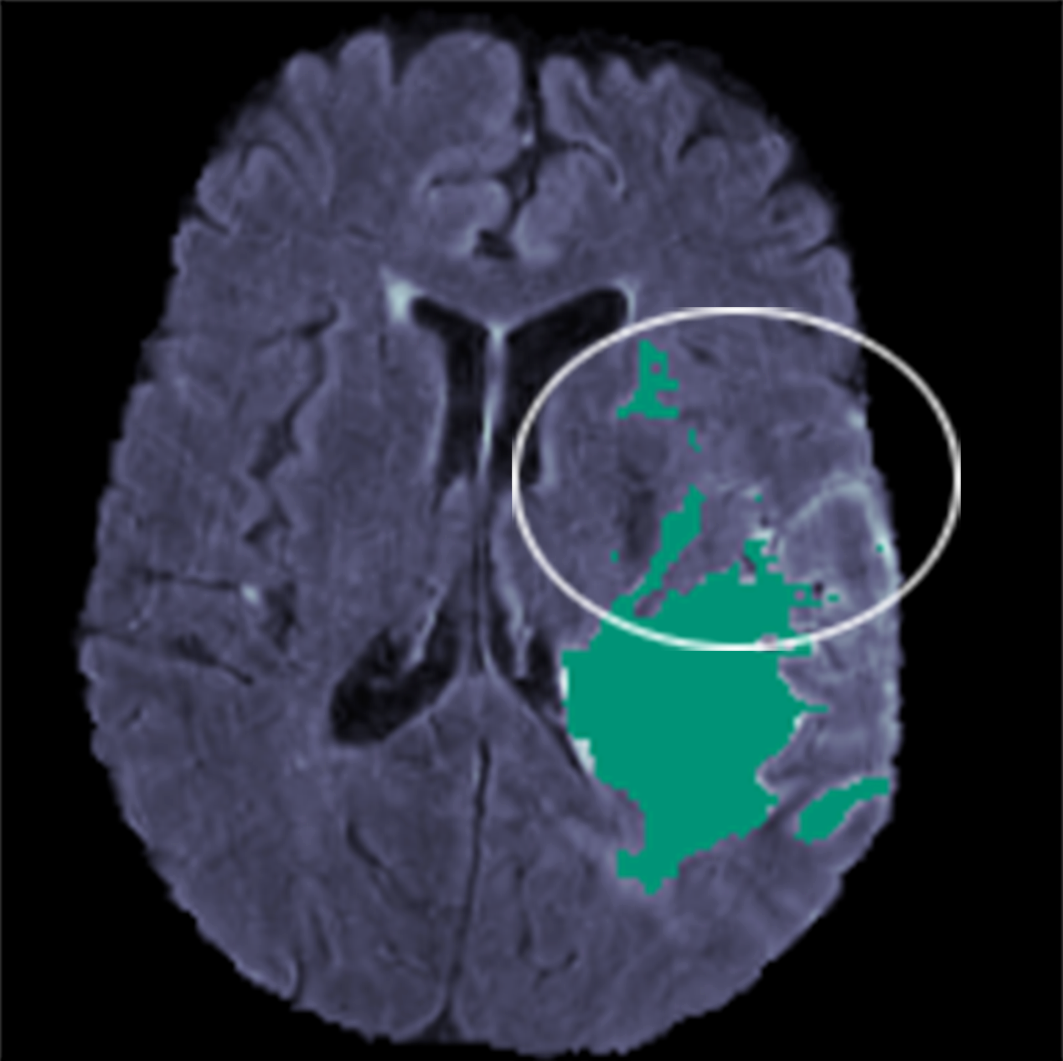

Despite this shortcoming, the attention mechanism demonstrated a notable strength: its ability to capture fine-grained details during segmentation - contingent on the MRI scan providing strong color contrast. This was evident in Figures 12(a) and 12(b), where the AttUNet produced a fine-grained segmentation of the lower half of WT (i.e., the looped areas) in the circled region. While this may be advantageous in some contexts, it could also suggest a tendency toward overfitting, as the model appears to trace lighter regions in the scan a bit too precisely, rather than learning the broader shape of the WT, which can comprise smaller and more discrete tumors that are irregular in shape (as shown by the top half of the circled region).

Refer to caption

(a) AttUNet WT Prediction

(b) Ground Truth WT Prediction

Figure 12: Comparison of WT predictions by (a) AttUNet and (b) Ground Truth